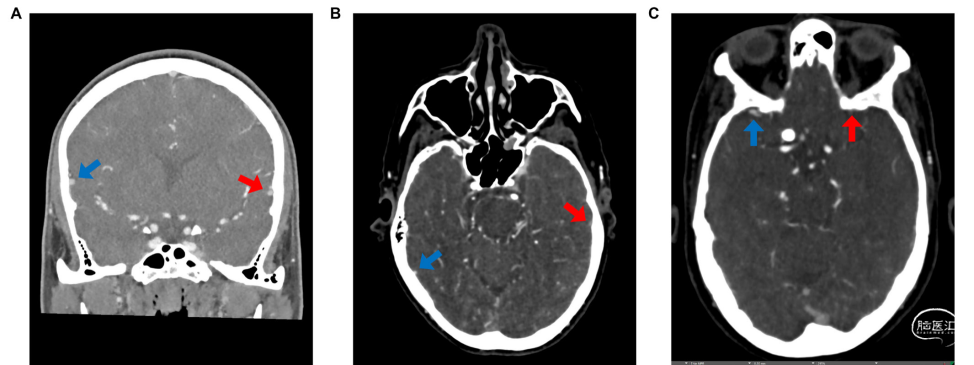

该研究收集2016年2月至2018年2月间佛罗里达大学收治的aSAH患者数据,分析患者入院时的CTA影像学和临床资料,比较静脉充盈减少与未减少的aSAH患者术后发生脑积水、血管痉挛、迟发性脑缺血(DCI)和预后情况。根据入院时和随访期间的CTA图像测量三个区域:大脑中浅静脉(SMCV)、蝶顶窦(SPS)和Labbé静脉(VOL)的HU值作为客观量化指标。静脉充盈评分如下:2,对称(静脉间密度差为<50%);1,不对称(静脉间密度差为>50%);0,无明显的管腔充盈(图1)。按皮质静脉充盈度评分比较脑静脉充盈状况,每条静脉0-2分,每侧半球COVES合计0-6分;时象选择在颈静脉球的HU不小于150HU,并通过DSA进行校正。

图1. 皮质静脉充盈评分的代表性图像。A. COVES 2分,左侧大脑中浅静脉(红箭头)与右侧(蓝箭头)对称;B. COVES 1分,左侧Labbé静脉(红箭头)与右侧(蓝箭头)不对称;C. COVES 0分,左侧蝶顶窦(红箭头)与右侧(蓝箭头)相比几乎不充盈。